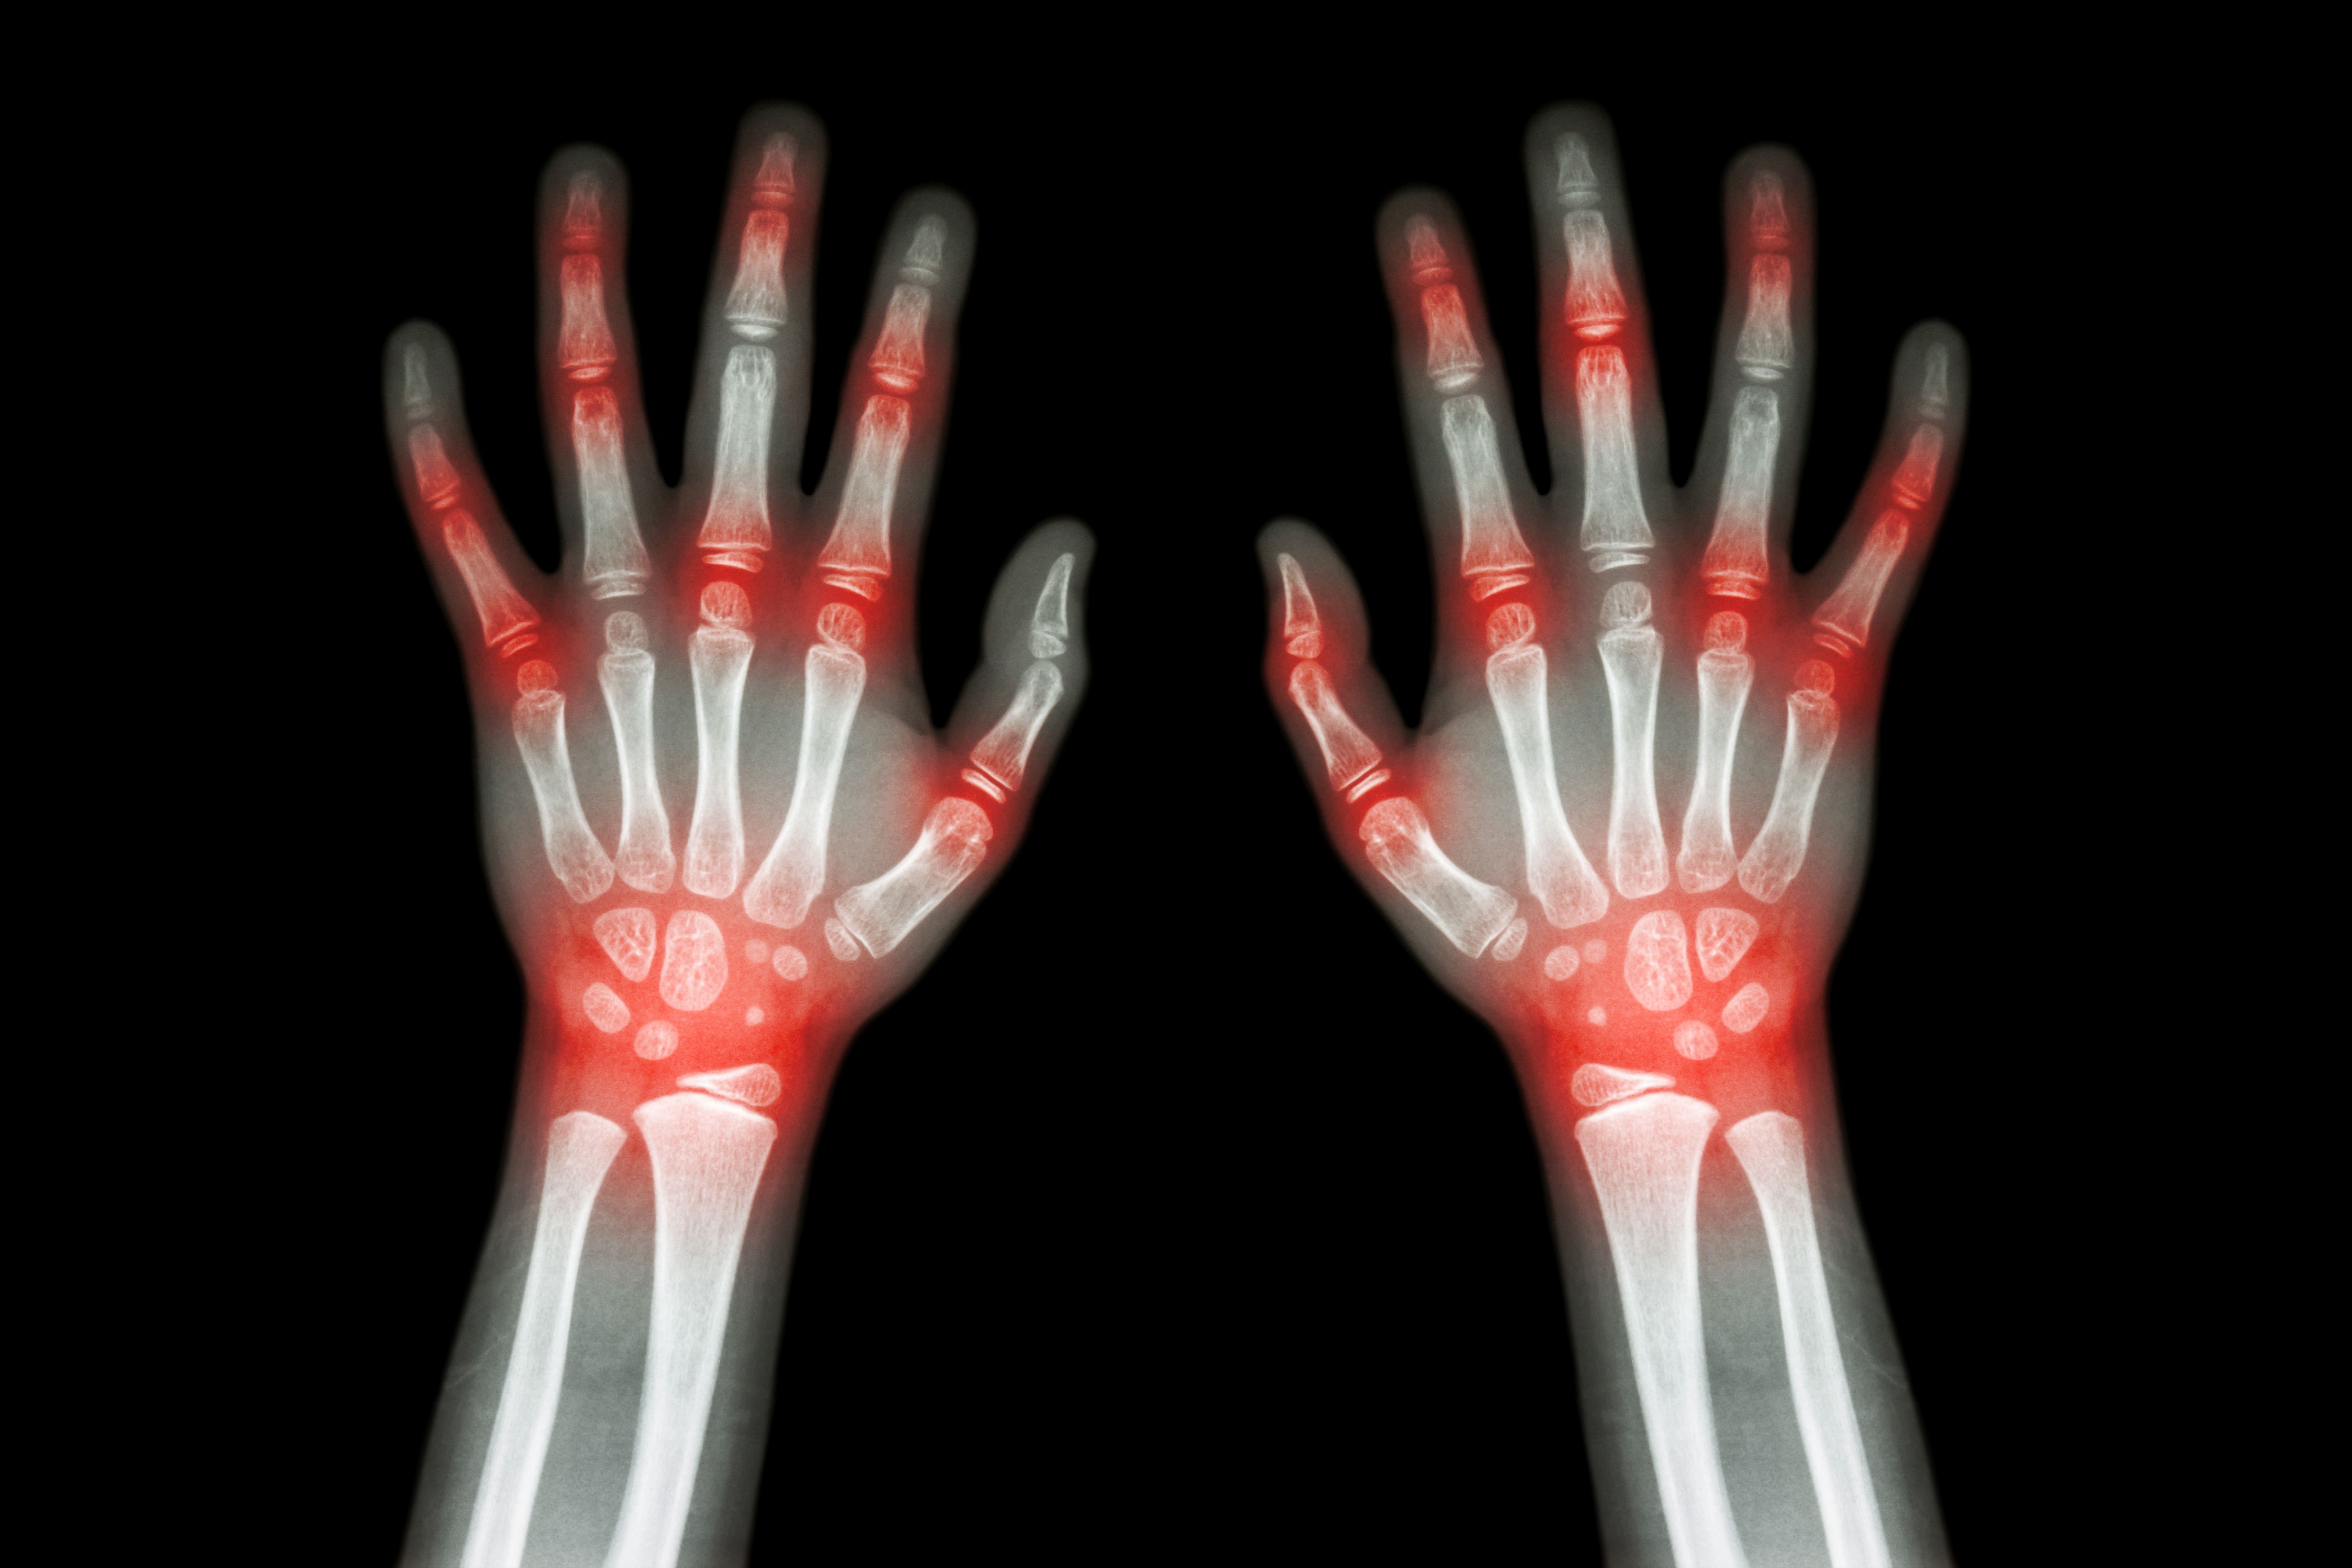

ABSTRACT: Dramatic progress has been made in our understanding of pediatric rheumatic disease. Various classification systems help identify juvenile idiopathic arthritis (JIA), which involves unique considerations that distinguish it from rheumatoid arthritis in adults. Vaccination issues are important for children with JIA. Renal involvement with systemic lupus erythematosus (SLE) is more common and more severe in children than in adults, but treatment of children who have SLE is similar to that of adults. Neonatal lupus erythematosus may occur in infants whose mothers have SLE. Juvenile dermatomyositis is associated with significant morbidity and mortality. Kawasaki disease is a common vasculitis of childhood, especially in infants and toddlers. Each of at least 8 major familial periodic fever clinical syndromes has specific distinguishing characteristics.